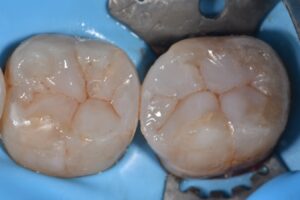

// Microlayers using #ClearfilMajestyES Flow for superficial layers and Majesty Esthetic flow in deeper layers

// Capping direct composite Majesty ES2 Universal #KurarayNoritake